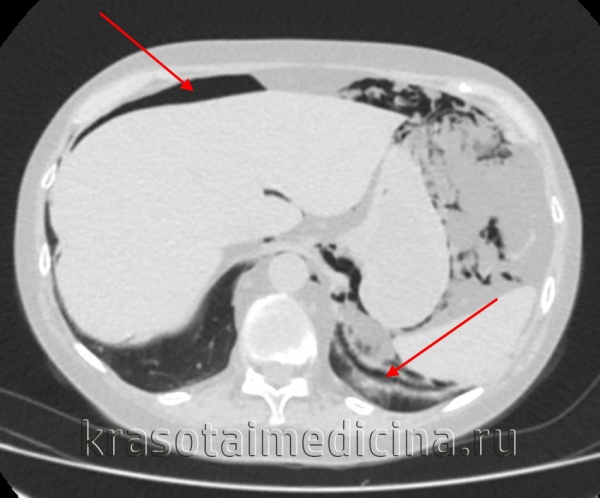

Обзорная рентгенография органов брюшной полости в вертикальном и боковом положении позволяет выявить свободный газ в брюшной полости, серповидно расположенный над печенью или под боковой стенкой живота. Данное исследование информативно в 80% случаев. Для более точной диагностики используют КТ органов брюшной полости (98% информативности) – позволяет обнаружить не только свободную жидкость и газ, но и утолщение желудочной и дуоденальных связок, непосредственно саму прободную язву желудка.